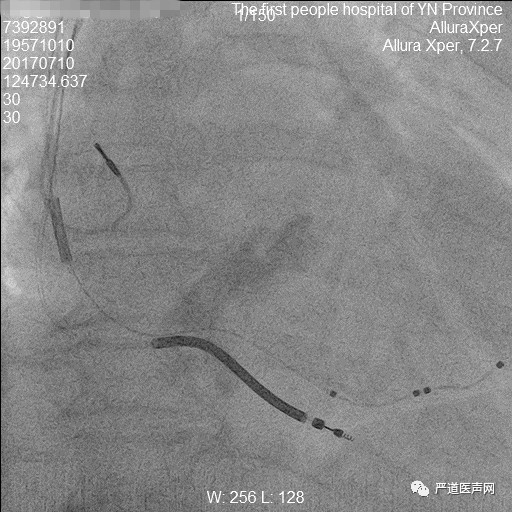

60岁男性,因活动后气促一年于2017年7月3日入院,既往有高血压病史4年,最高血压150/90mmHg,自服降压药物,血压控制在130-140/70-80mmHg。查体:BP 110/70mmHg,颈静脉充盈,双肺呼吸音粗,双肺底可闻及湿罗音,心界向左下扩大,双下肢浮肿。心脏彩超显示左心房扩大4.0cm,左心室舒张末内径6.5cm,EF 27%,室壁弥漫性运动减弱。诊断为扩张型心肌病,心功能III级,三度房室传导阻滞,高血压I级。

手术要点:

长鞘顺利进入冠状窦,冠状窦逆行造影显示静脉夹层。随后行冠状动脉造影观察冠状窦开口情况,可见真假腔显影,通过右冠造影管在长鞘支撑下找到冠状窦口,重新观察造影后,只见真腔显影,长鞘顺利进入真腔后,成功植入左心室电极。术后心电图示QRS 132ms。术后规律服药后心功能明显改善,10个月行心脏彩超提示LVD 55mm,EF 0.45。

18.jpg

冠状动脉造影显示冠状窦

19.jpg

长鞘进入真腔

20.jpg

逆行导丝

21.jpg

成功置入三根电极